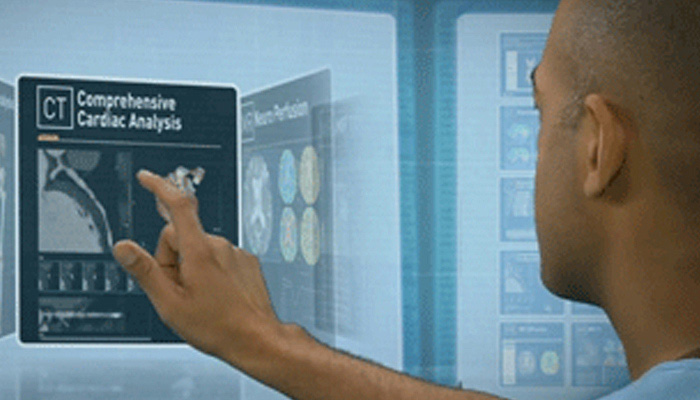

تشهد حاليًا خيارات العلاج التي لا تتطلب سوى تدخل جراحي محدود في القلب والأوعية الدموية انتشارًا ملحوظًا. ولقد ساهمت التطورات الأخيرة في مجالات التشخيص والتوجيه بالصور المباشرة Live Image Guidance والمعلوماتية في جعل هذا الأمر ممكنًا. بالتعاون مع أشهر أطباء أمراض القلب، ابتكرنا حلولاً تساهم في منح المرضى الفرصة لتغيير حياتهم. فهذه الحلول تساعد في تسريع سير العمل وزيادة فعالية الطاقم الطبي وتوفير أفكار سريرية.

تعلّم كيف تستطيع الحلول التي ابتكرناها في مجال طب القلب مساعدة مؤسستك